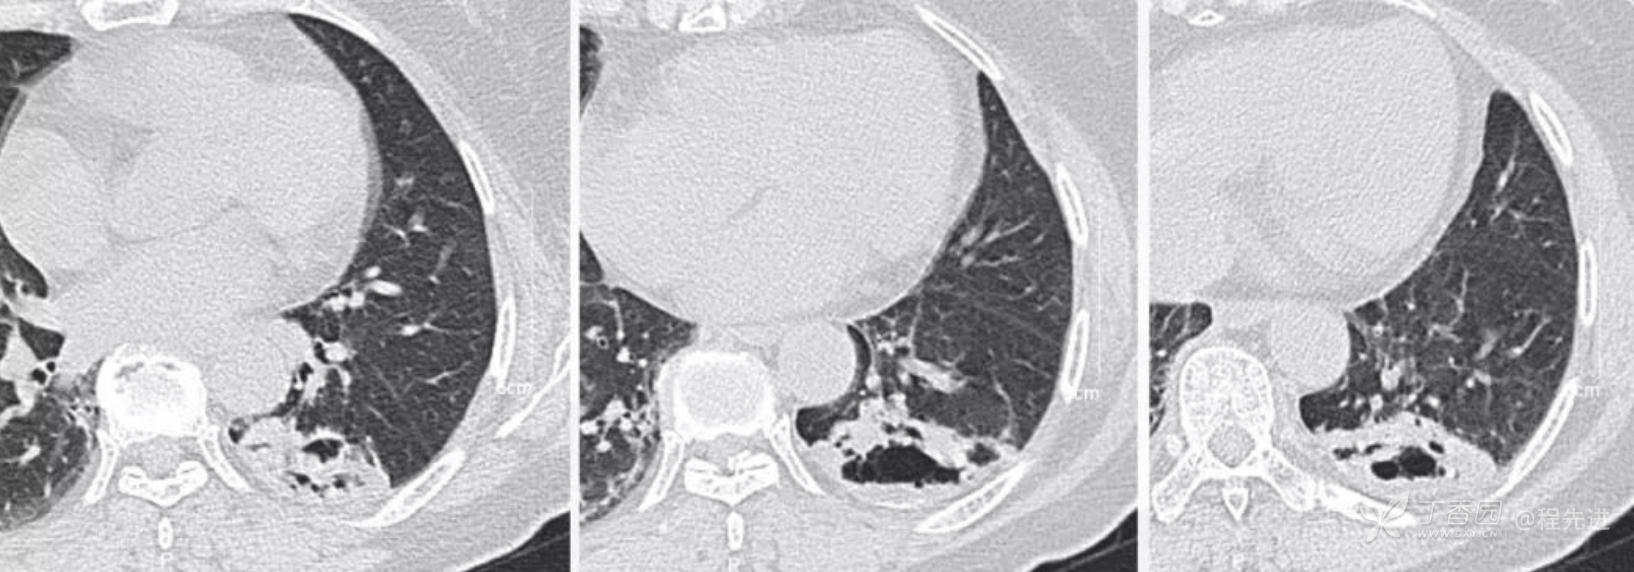

肺窗